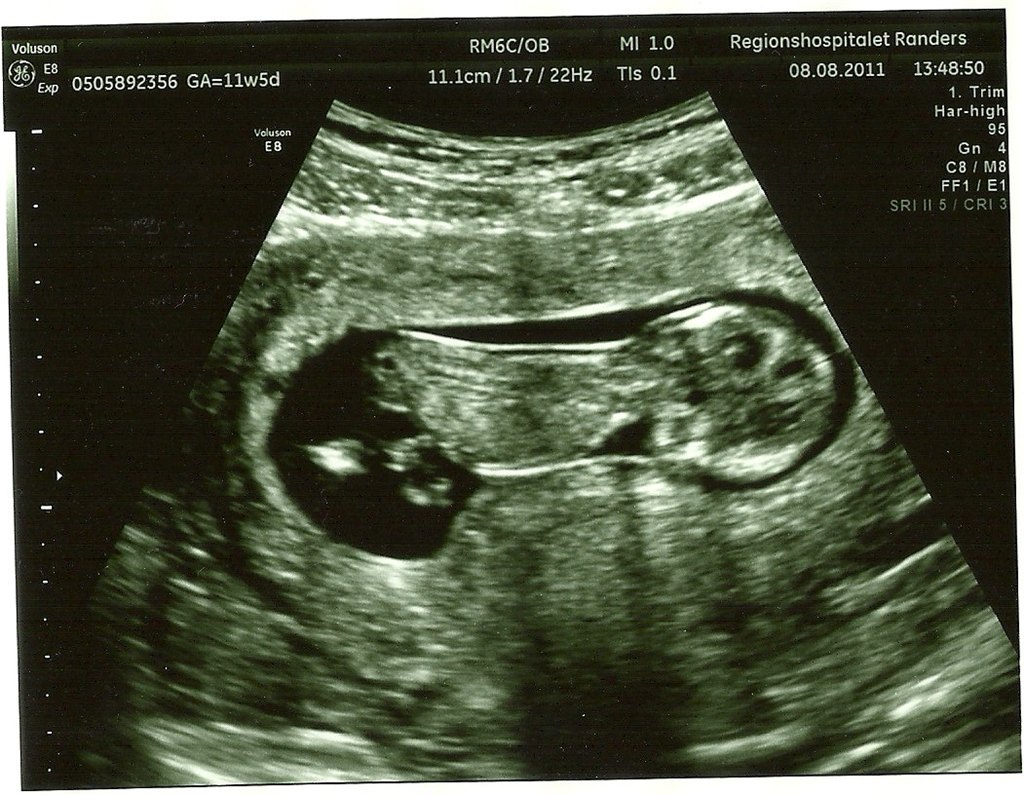

Den 9 september kl 10.00 skal jeg til første scanning med maven og vi glæder os sindssygt meget!

Jeg kan regne frem at jeg så er 12+2 så det er helt perfekt

Hvornår var I til scanning og vil I dele jeres flåååårtte NF-billeder så jeg rigtig ka glæde mig endnu mere